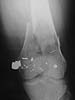

Use 6.5 mm cannulated screws if you have and place one anterior to where IMN will go if anterior cortex if insufficient and AP screws on either side of the IMN out of the trochlea to provide some additional varus/valgus stability. I worry about the leg going into valgus w/ the lack of lateral cortex.

See attached case that was done several years ago before LISS. He had comminuted trochlea and anterior blocking screws were used to prevent anterior IMN cut-out.

Yesterday antegrade closed nailing was performed (UFN 10 mm). Two cancellows screws added to fix the lateral condyle. The surgery was not too easy, and extension of condylar part i failed to reduce completely. The shaft looks even more ugly. The patient left for a couple of days in 90/90 position. Comments/opinions/advices are welcome.